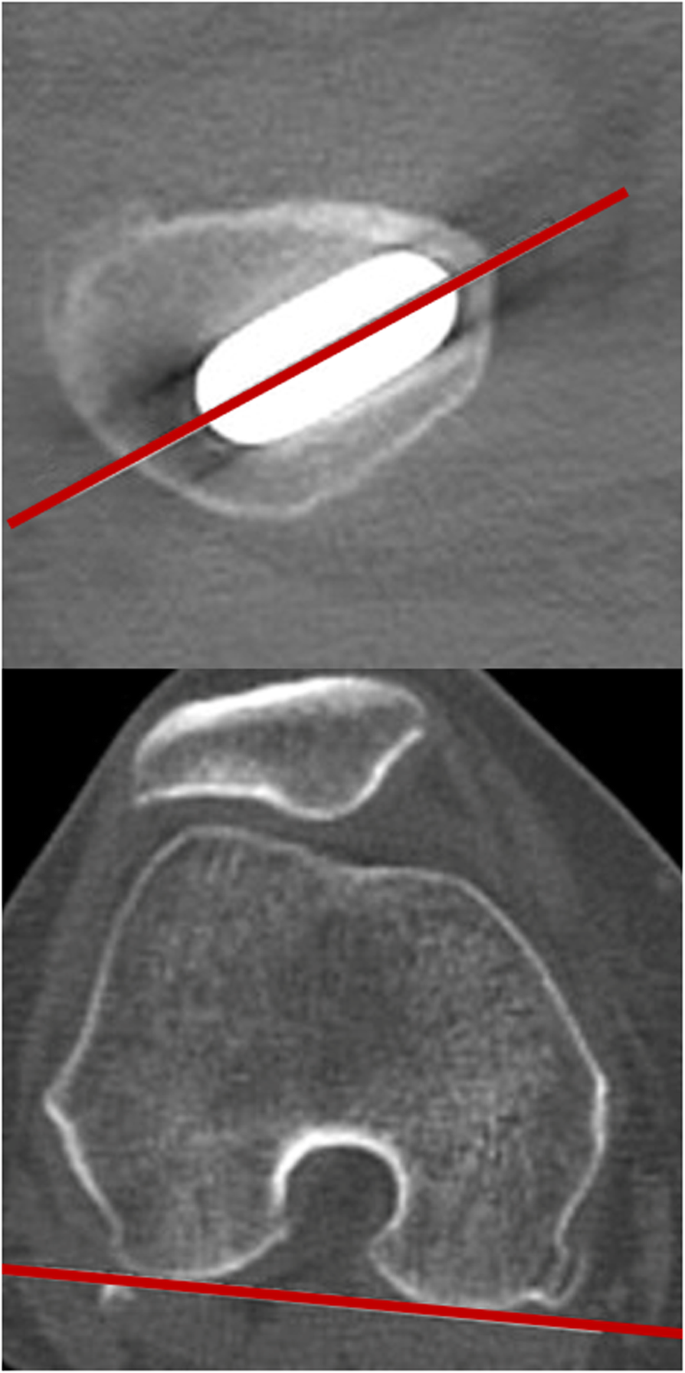

We evaluated anteversion of the femoral stem on axial CT scans taken with the patient in a supine position, from the pelvis to distal femur, using a metal artifact removal method. The anteversion angle was measured as the angle between the stem-neck axis and an axis parallel to the posterior aspect of the femoral condyles, measured in the transverse plane (Fig. 3) [20].